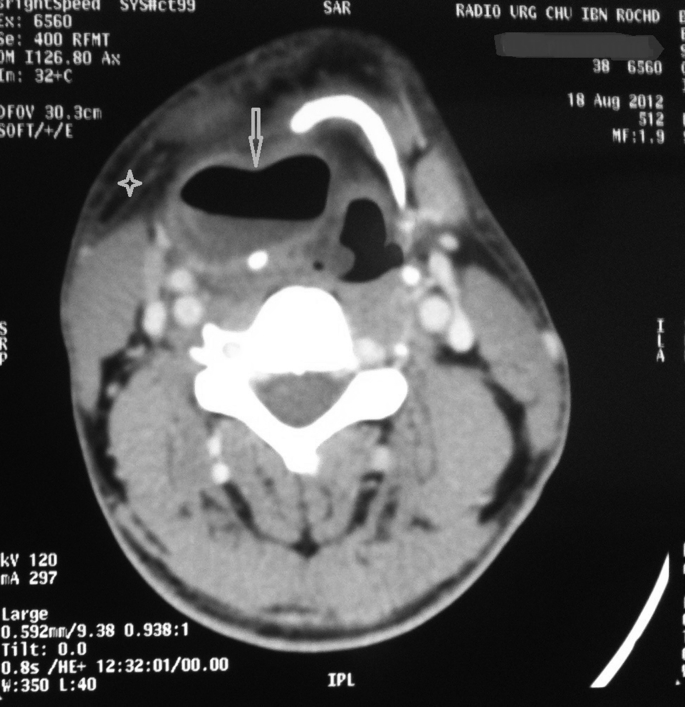

A fine needle aspiration assessment was performed on the neck swelling. This produced air with 15ml of frank pus that was submitted for microscopy, culture and sensitivity testing. High-dose on a course of intravenous Metronidazole and Ceftriaxone were commenced. An urgent CT scan of the neck (Fig. 1, Fig. 2) showed a large right-sided combined pyolaryngocele associated with regional and subcutaneous neck infections. Intravenous antibiotic therapy was continued for one week.

A computed tomography scan revealed a cystic lesion with a hydroaeric level (arrow) in the axial images (Fig. 1) And an intra-extra laryngeal component on the right side with extension through the thyrohyoid membrane of 5 Cm × 3 Cm × 2.5 Cm which could be determined in the coronal sections (Fig. 2), with airway collapse, compatible with a superinfected mixed laryngocoele, associated with emphysema in the deep planes of the neck (asterisk).